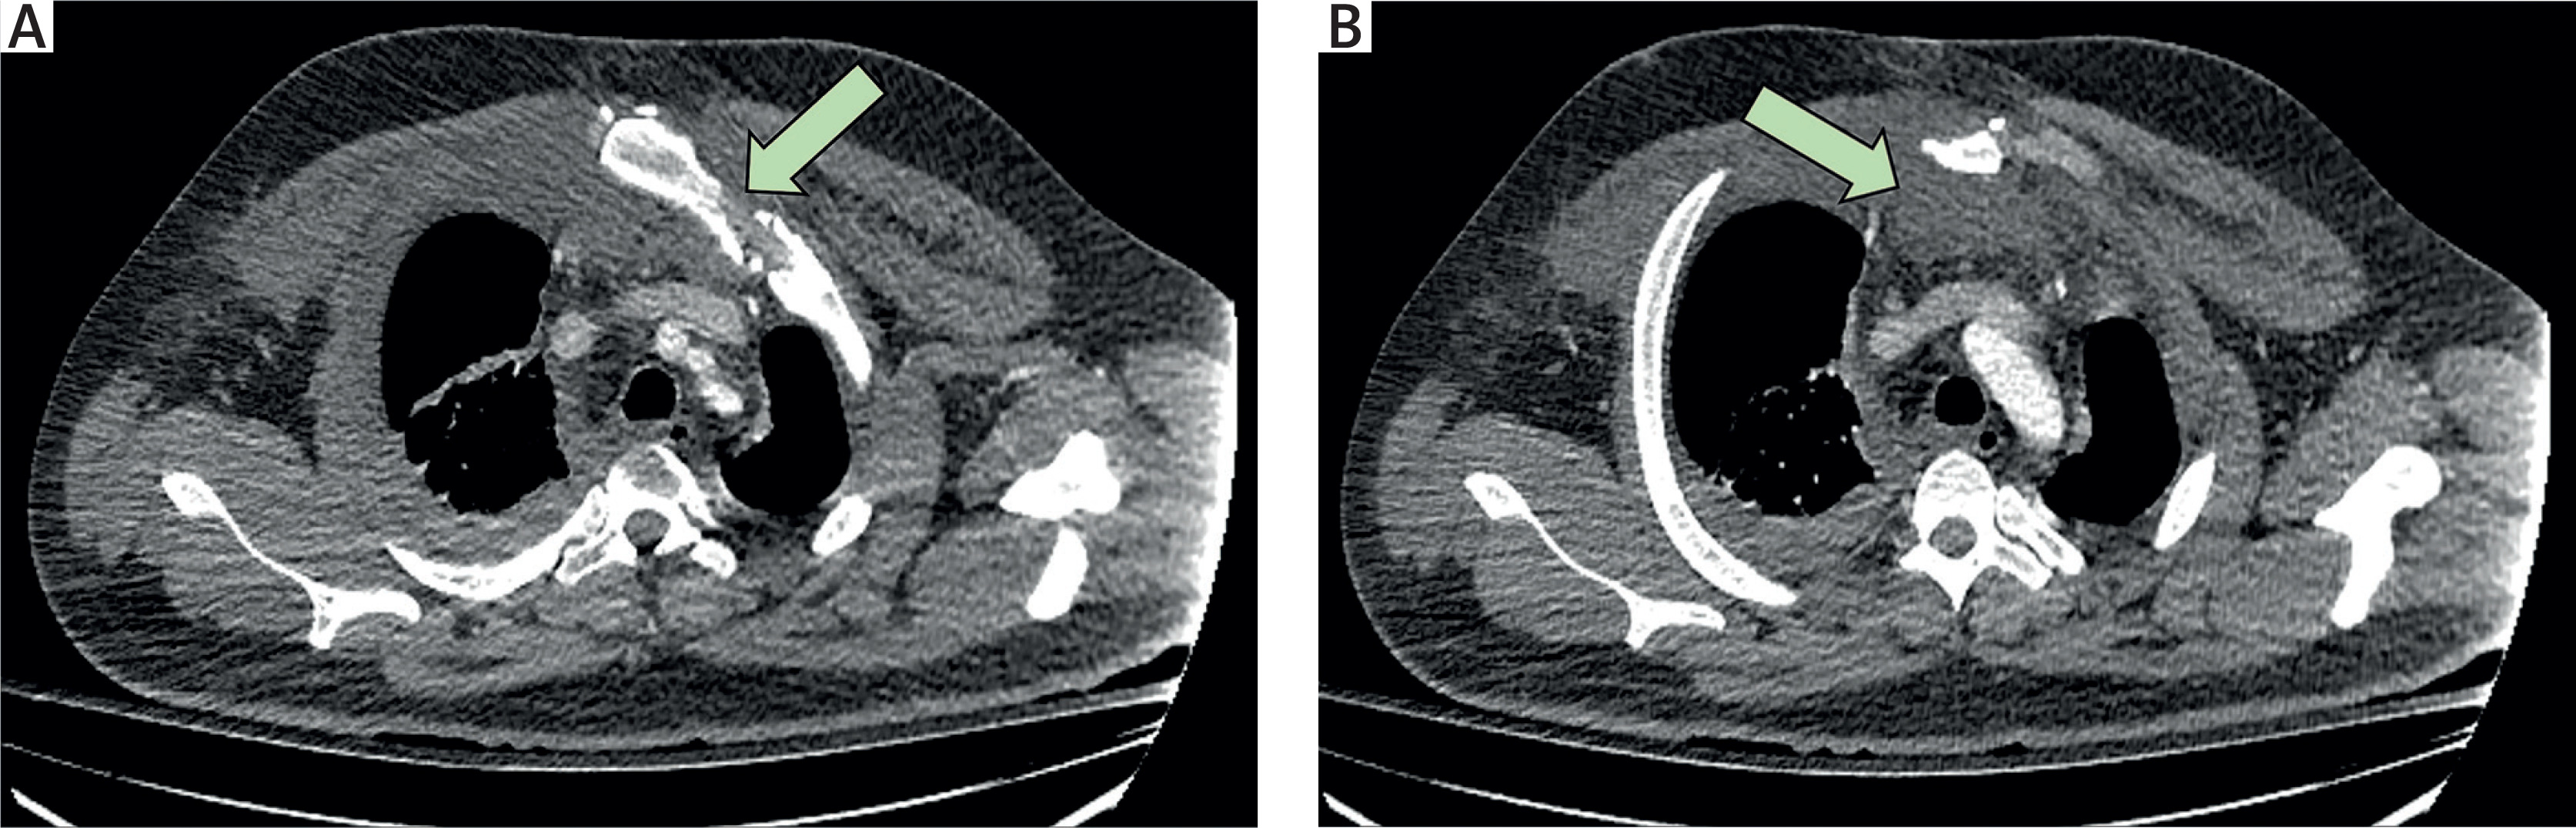

A 33-year-old male was transferred from a regional hospital after a high-impact motor vehicle collision that resulted in the death of the driver. On arrival, he was haemodynamically stable with a Glasgow Coma Scale (GCS) score of 15/15 and was assessed by a multidisciplinary trauma team. Imaging demonstrated a left hip dislocation, a displaced sternal fracture – manually reduced in the emergency department and temporarily stabilised with skin traction – multiple rib fractures (right 4th–8th, left 6th–7th), flail chest, pulmonary contusion, and a sizable retrosternal haematoma without active bleeding (Figure 1). Additionally, the patient had deep lacerations on the anterior aspects of both knees, which were sutured in the emergency department.

Figure 1

Preoperative computed tomography (CT) images demonstrating: A – displaced manubriosternal dislocation, B – associated retrosternal haematoma